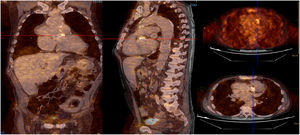

The results obtained in this study show that 18F-FDG PET for the diagnosis of IE in patients with prosthetic valves and intracardiac devices is a useful technique to obtain a rapid diagnosis, particularly in patients whose TEE images are doubtful, inconclusive or even negative (Figure 4).

Infective endocarditis (IE) in a mechanical aortic valve in a 68-year-old male with a history of Bentall procedure and intermediate suspicion of IE. On transesophageal echocardiography, an aortic pseudoaneurysm was observed in the valvular plane with a diameter of 67 mm×44 mm and with an image of a thrombus inside. On 18F-FDG PET study, hypermetabolism was observed in the mechanical aortic valve with SUVmax of 4.49 g/ml.